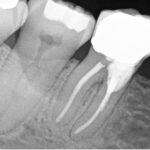

- October 14th – Resorption repairs were done on teeth #27, #29, and #30

- December 21st – A follow-up scan showed that the molar was still doing well, and the bicuspids looked healthy

- December 27th – Endodontic treatment (root canal) was performed on tooth #19, along with surgical repairs on teeth #19, #20, and #22

We used a full-mouth scan to monitor this case. While this gave us a broad view, it doesn’t provide the same fine detail as a limited field of view scan. There were some artifacts (image distortions) from previous repairs on the right side, but the left side images were clearer.

Why Does Bilaterally Symmetrical Resorption Happen?

When resorption happens on both sides of the mouth in a similar pattern, it raises the possibility of a genetic link. Other possible causes include:

- Past trauma to the teeth

- Effects from orthodontic treatment (braces)

- Individual factors that make certain teeth more vulnerable